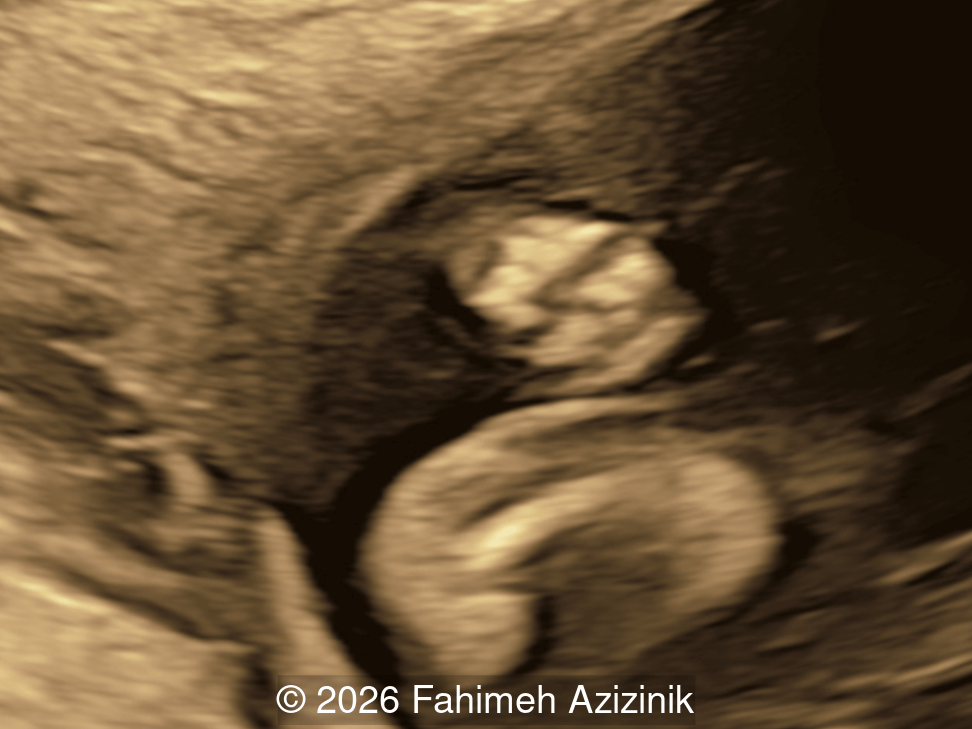

Image 3

• Complex syndactyly of the hands and feet. Complex hand brachysyndactyly with “mitten-like” appearance due to bony fusion of the fingers

Bicoronal synostosis is the characteristic cranial hallmark of Apert syndrome, detectable sonographically from 18 weeks. Its most recognizable manifestation is turribrachycephaly, defined by an elevated cephalic index (typically >85–90%) and a tall cranial vault with marked frontal bossing [19]. On prenatal ultrasound, the face in Apert syndrome shows midface hypoplasia with a depressed nasal bridge, proptosis, hypertelorism, and frontal bossing. The extremities demonstrate syndactyly of both bone and soft tissue of the hands and feet with partial-to-complete fusion often involving second, third, and fourth digits, known as “mitten hands” and “socked feet”. In severe cases, all digits are fused, with the presence of a single nail known as “synonychia” [20]. Other ultrasound findings include mild ventriculomegaly, agenesis of the corpus callosum, deficient or absent septum pellucidum, and fusion of the cervical vertebrae at the level of C5-C6 [21]. Cardiovascular (atrial and ventricular septal defect) and genitourinary anomalies (hydronephrosis, and cryptorchidia) are present in 10% of patients [22]. Increased nuchal translucency in the first trimester [23], widely open metopic suture [24], and polyhydramnios [25] have also been reported. Three-dimensional (3D) ultrasound facilitates assessment of surface abnormalities of the face and extremities, and magnetic resonance imaging (MRI) can be used to evaluate associated intracranial conditions [26].